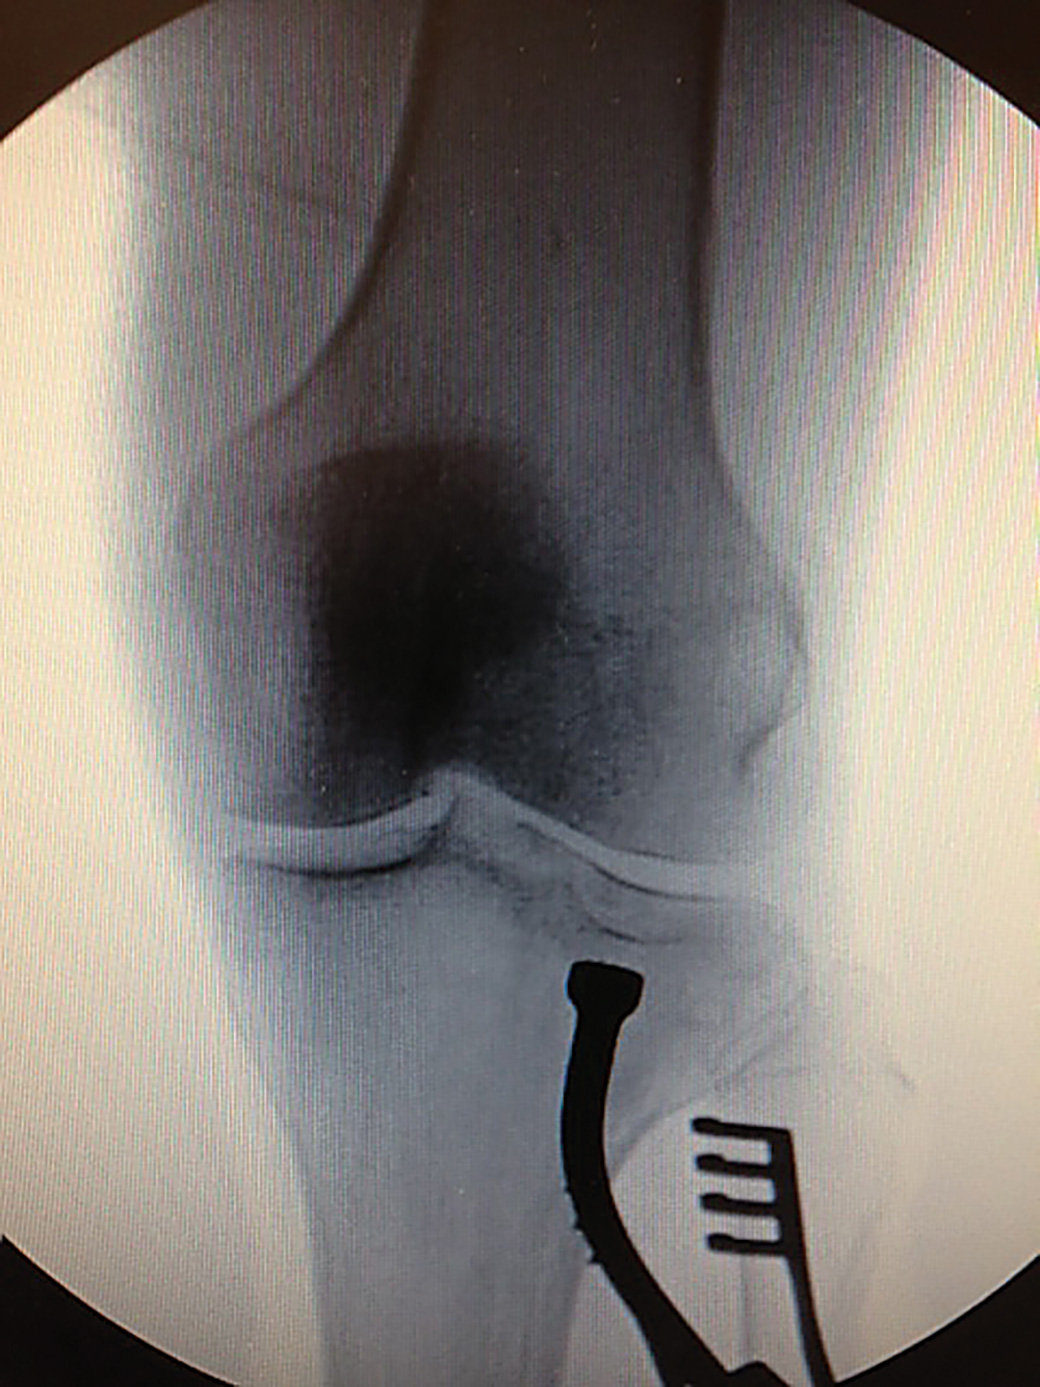

Designed to help with indirect reduction of a depressed tibial plateau fracture, and can be used with arthropscopic visualization and percutaneous fixation